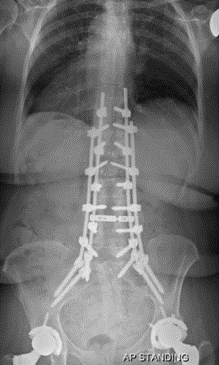

图7 术前-术后1个月-术后1个月外观